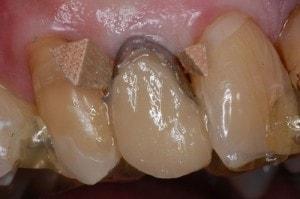

Greater Curve standard in place

Matrix trimmed labially. Contact openings made. Wood wedges are lightly placed to secure the matrix only. The wood wedges are not used to force the teeth apart. Wedging in the traditional sense is not necessary, since the contacts will be a direct build against the adjacent teeth. In lieu of using a retainer Triad Gel holds the matrix in the proper position.

first increment of flowable

Matrix held against the mesial of #6 while the first increment of flowable was placed. This procedure locks the matrix against the mesial of #6.

Completed build up

Premise A3.5 Opacious and Premise A3.5 Body complete the Build Up.